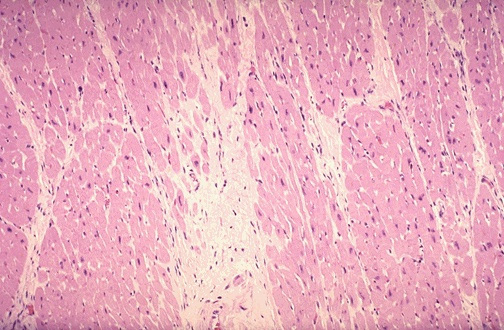

The following images are representative of her myocardium at different times. Match the image to the time course of her cardiovascular disease.

Figure 6: Representative appearance of her myocardium

Figure 7: Representative appearance of her myocardium

Figure 8: Representative appearance of her myocardium